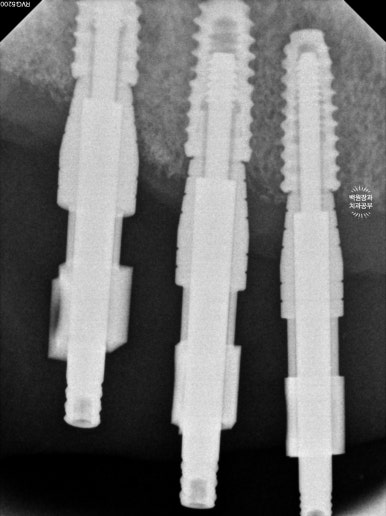

임플란트가 잘 고정되었는지 Osstell을 이용하여 ISQ 수치를 측정하고, impression coping을 연결하여 임플란트 인상채득을 시행합니다.

이렇게 임플란트 뽄을 뜨고나면, 드디어 임플란트에 연결할 맞춤형 기둥 (custom abutment)과 임시치아를 만들어오게 됩니다.

임시치아를 연결하고나면, 이제 씹는 연습을 하게 됩니다.

엑스레이를 보시면, 티타늄 재질의 오스템 임플란트 정품 !!! 맞춤형 지대주 (custom abutment)가 연결되어 있는 것을 보실 수 있을거에요.

맞춤형 지대주를 만들어지는 치과는 많아졌으나, 오스템임플란트의 정품 티타늄으로 만들어졌는지 꼭 확인하세요.

이렇게 맞춤형 지대주를 만들어드리면, 보다 조화로운 보철물을 만들 수 있어 예쁘고 음식물이 덜 끼는 훌륭한 보철물을 위한 포석이 마련됩니다.